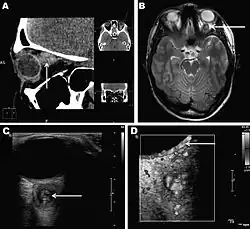

Infections in humans[3] usually manifest as a single subcutaneous nodule, which is caused by a macrofilaria that is trapped by the immune system. Subcutaneous migration of the worm may result in local swellings with changing localization. In addition, rare cases of organ manifestation have been reported, affecting the lung, male genitals, female breast, or the eye. The latter is found in particular during the migratory phase of the parasite. D. repens occurs more commonly in adults (aged 40–49 years). The only exception is in Sri Lanka, where children younger than nine years are most likely to be infected. The youngest individual reported was aged four months.[4]

Final diagnosis is established by microscopic examination of the excised worm. Making a definite species diagnosis on morphologic grounds is difficult, because a large number of zoonotic Dirofilaria species have been described that share morphologic features with D. repens.